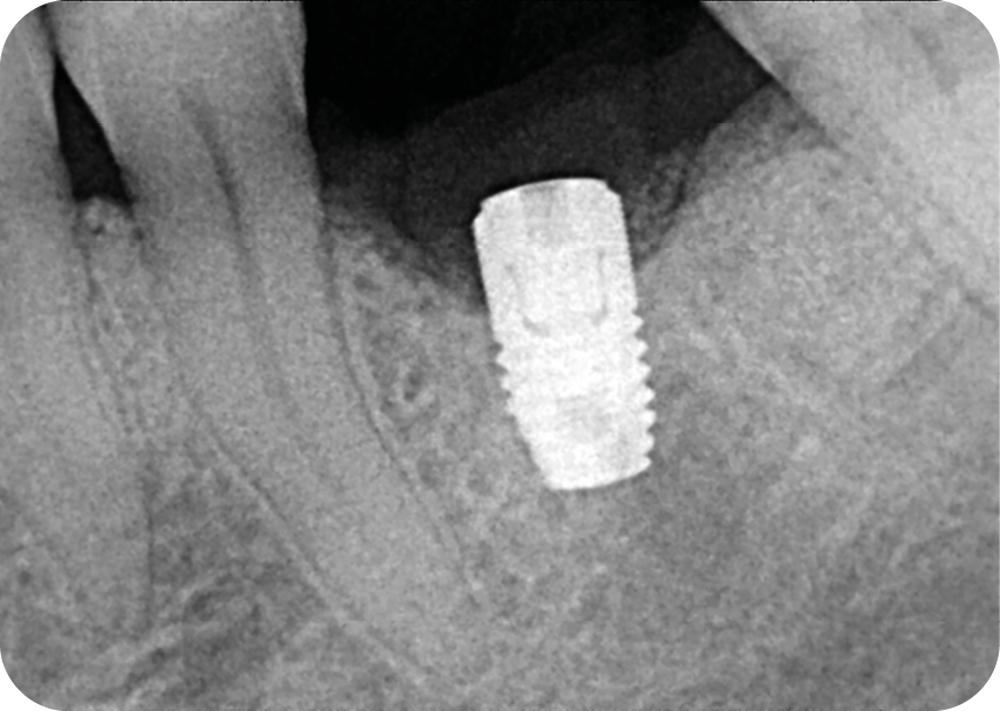

- Un implant posé en 2018 après la fin du traitement orthodontique

- Péri-implantite diagnostiquée en 2021

Chez ce patient, le traitement de la péri-implantite a comporté une chirurgie associant décontamination électrolytique de la surface implantaire, régénération osseuse guidée et enfouissement de l’implant. Le résultat à 2 ans est très moyen au vu du pourcentage de régénération osseuse obtenu. Comment peut-on prévoir un tel résultat alors que l’on a suivi les recommandations à la lettre, que l’on a utilisé les dernières technologies de décontamination, que l’on y a mis tous les moyens, que le patient est en bonne santé générale et qu’il vient en plus régulièrement aux séances de thérapeutique de soutien ? Le succès du traitement des péri-implantites n’est pas simple à obtenir, surtout quand un élément clé est compromis… la maintenance personnelle ! En effet le succès n’est possible que si le contrôle de plaque quotidien est optimal et, ici, ça n’était pas le cas. Le patient se brossait certes les dents, mais ne passait pas quotidiennement les brossettes, ce qui…